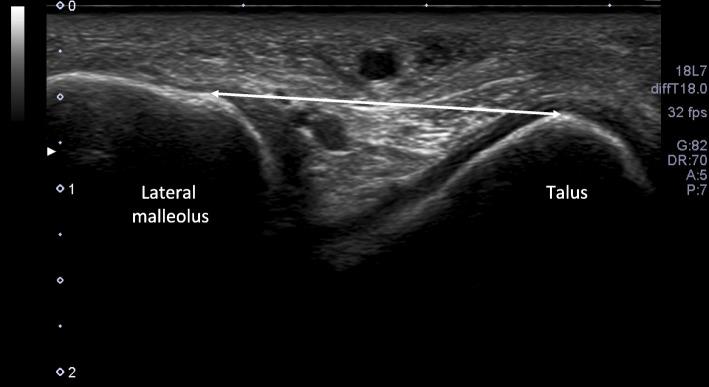

Participants were 14 female college students (21-22 years) with normal menstrual cycles (cis gender). Anterior drawer stress to a magnitude of 120 N was applied for all participants. Anterior talofibular ligament (ATFL) length was measured as the linear distance (mm) between its points of attachment on the lateral malleolus and talus using ultrasonography. Data on ATFL length from each subject were used to calculate each subject's normalized length change with anterior drawer stress (AD%). The University of Tokyo method was used for evaluation of GJL. AD% and GJL were measured once in each menstrual phase.